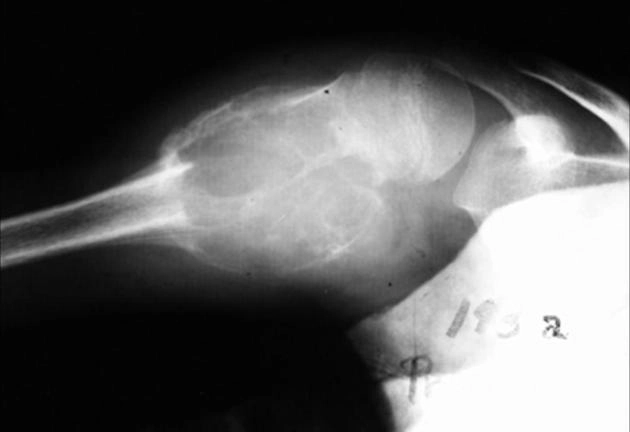

Nang xương đơn giản (Simple Bone Cyst - SBC)